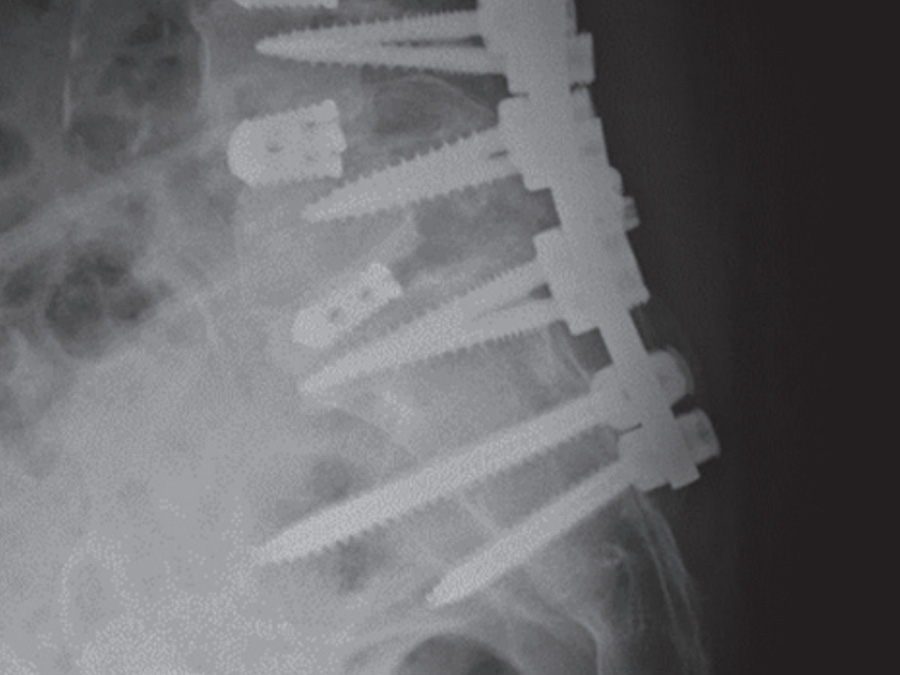

フツロメディカルは、脊椎などのインプラントを中心に高品質な医療機器を提供する専門商社です。患者さまの未来と医療現場の信頼を、確かな製品と迅速な対応で支えます。